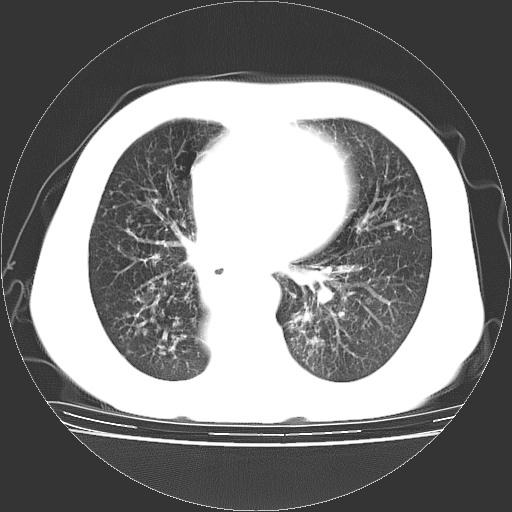

女,70岁,咳嗽、咳痰一个月,低热一周。

1.左上肺结核,部分纤维化。右肺中下叶部分肺不张,内见液化、坏死及点状钙化,右中下叶支气管壁增厚、管腔狭窄,见多个点状钙化,结合临床考虑支气管内膜结核,建议痰检查抗酸杆菌并参考血沉。两肺多个小圆点状高密度灶,境界模糊,多考虑结核肺内播散。但本人年龄较大首先应支气管镜检以除外右肺癌。

3、两肺肺结核(右肺下叶背段及左肺)。